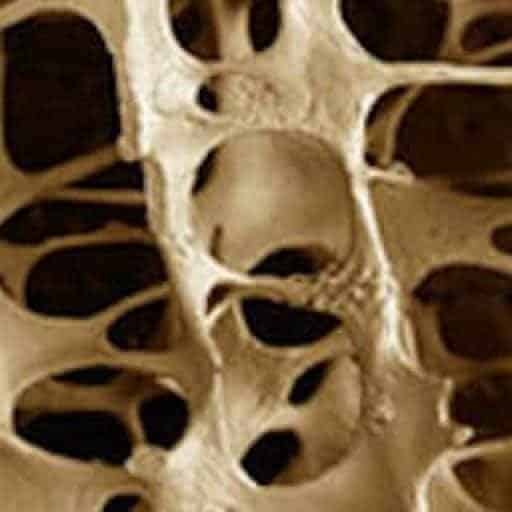

Hvad kan vi selv gøre, for at forebygge Osteoporose (knogleskørhed)? – en sygdom som desværre først giver symptomer, når den er ret fremskreden.

Foredraget denne mandag handler om hvad Osteoporose er. Hvilke gener er der, og hvilke problemer medfører sygdommen. Hvordan diagnostiseres sygdommen. Hvilke risikogrupper – hvem rammes, behandlinger og forebyggelse, er noget af det, du vil få mere at vide om.